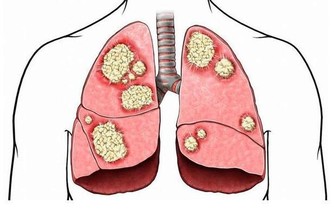

對於以性養生的好處,在成書於晉代之前的中國性學古籍《玉房秘訣》中便已有記載:“以陽養陰,百病消除,顏色澤悅,肌好,延年不老,常如兒童”。現代醫學研究進一步驗證了這種說法,蘇格蘭皇家愛丁堡醫院的研究發現,性會使女性看起來年輕12歲。更早一點的研究發現,性生活可以促進雌激素分泌,讓皮膚更光滑,頭髮更亮澤。此外,在性愛的過程之中,人體的壓力隨著體內荷爾蒙的釋放而釋放,有利於氣血運行和促進睡眠。